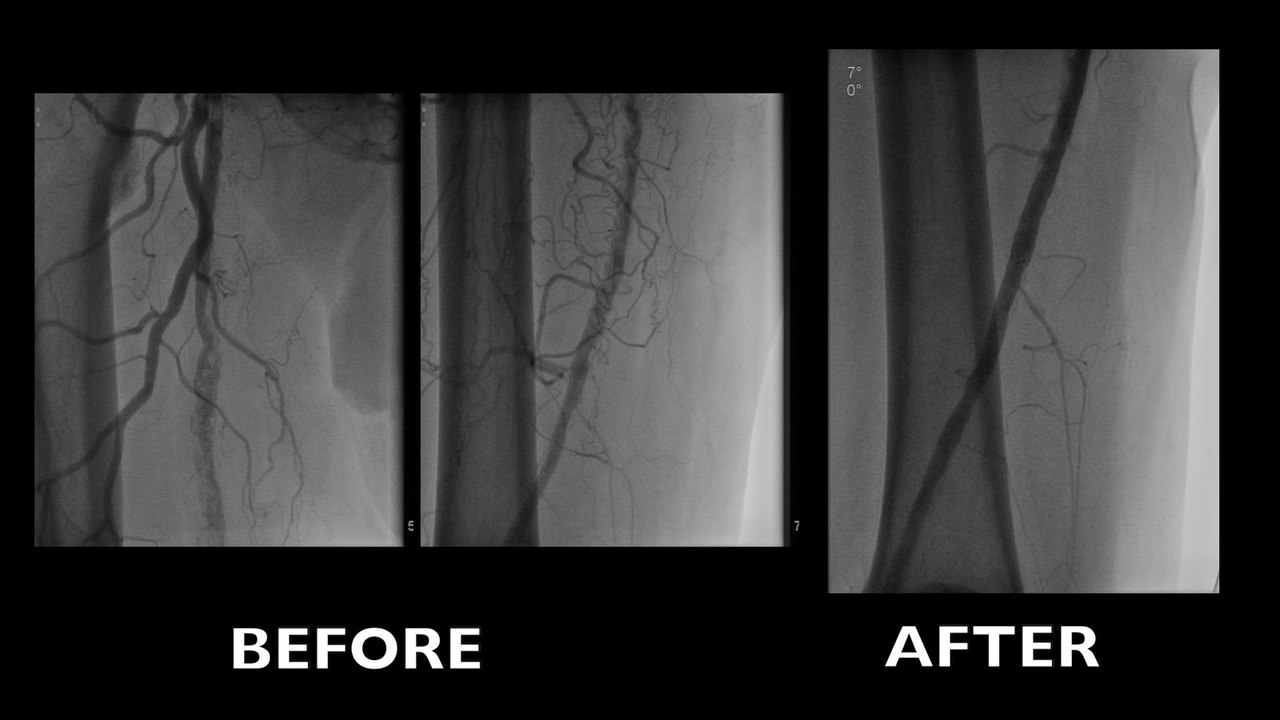

Current treatment of the Superficial Femoral Artery (SFA)

Can we really do without leaving anything behind or do we still need a scaffolding?